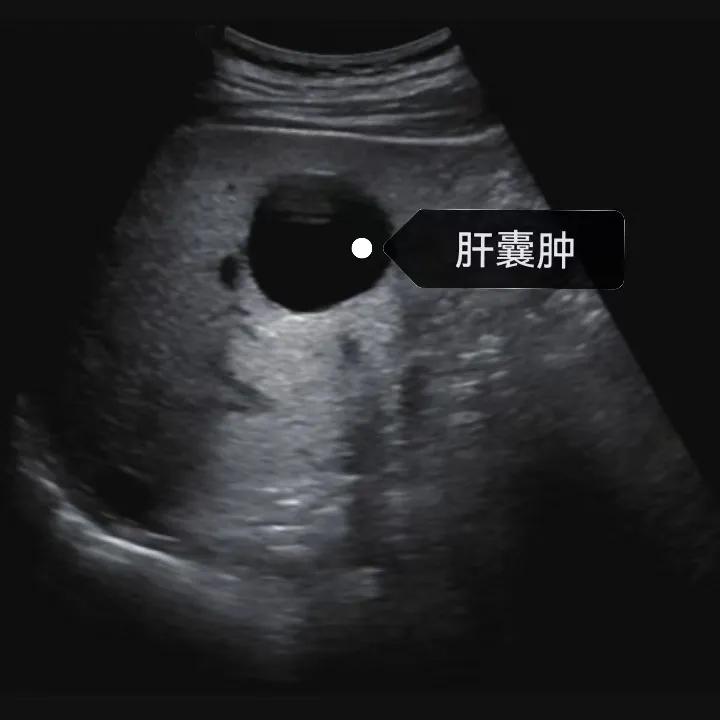

漯河市中醫(yī)院健康科普:認識肝囊腫

隨著人們健康意識的提升,越來越多的人每年會進行健康體檢,由于腹部(肝膽胰脾)超聲作為常規(guī)體檢項目之一, 肝囊腫的檢出率也愈發(fā)升高,大部分人對“腫”字都比較困惑,今天我們就來一起了解一下肝囊腫。

肝囊腫是一種常見的肝臟良性疾病,呈圓形或橢圓形,外由上皮細胞包裹形成包膜,內(nèi)由清亮、無色、無細胞成分的囊液填充,看上去就像是一顆注滿了水的氣球,因此通俗一點說就是肝臟中的“水泡”。

超聲通常是診斷肝囊腫的首選方法,彩超對肝囊腫的檢出率可達98%,<1cm的囊腫也可檢出。肝囊腫常表現(xiàn)為圓形或橢圓形無回聲,包膜光滑完整,邊界清晰,可有側(cè)壁回聲失落征象,后方回聲增強。病程長、囊腫較大者或囊內(nèi)有過出血、感染者,無回聲腔內(nèi)可見少量絮狀回聲漂浮。超聲對肝囊腫的診斷準確而靈敏,且方法簡單、無創(chuàng)、費用低、可重復性高,因此常常被作為首選。